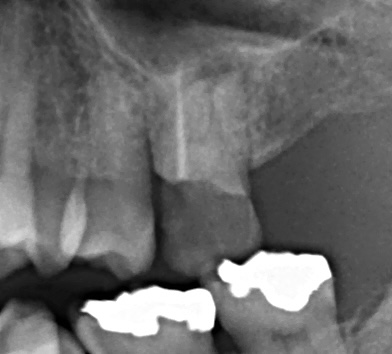

レントゲンを見ると歯は失活歯で口蓋根にメインポイントが1本入っていますが頬側根は手付かずのようです。

取れた詰め物は再利用できなかったので、患者さんには再度根管治療からやり直すことを提案し同意を得ました。根管口付近を慎重に探っていくと頬側根の入り口が見つかりました。